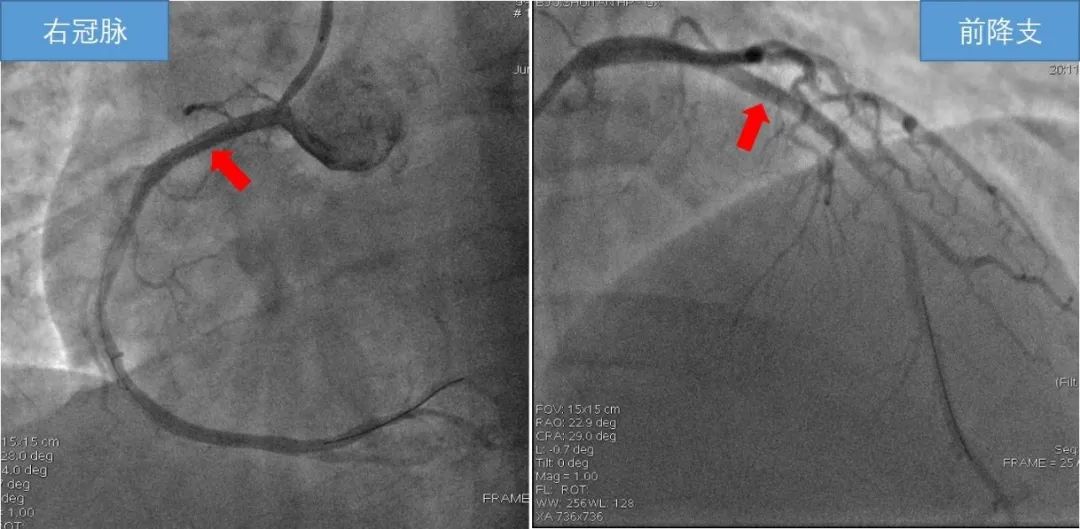

根据冠脉造影显示,患者的梗死血管右冠状动脉近端经过溶栓已经开通,但仍残余90%的狭窄,而前降支有95%的狭窄,而且病变相当不稳定。为了获取最好的预后,心内科刘巍主任团队在开通右冠状动脉后,又开通了非常重要的前降支。不到30分钟,手术成功,患者意识转清,心跳恢复稳定,血压上升,胸痛胸闷症状消失,转入监护病房进一步治疗。近日,王先生已顺利出院,“谢谢你们帮我捡回了一条命。”

造影提示前降支和右冠脉存在重度狭窄,右冠脉近段经溶栓后再通,仍存血栓影。

患者冠脉介入术后,右冠脉及前降支狭窄消失,恢复正常血管直径。